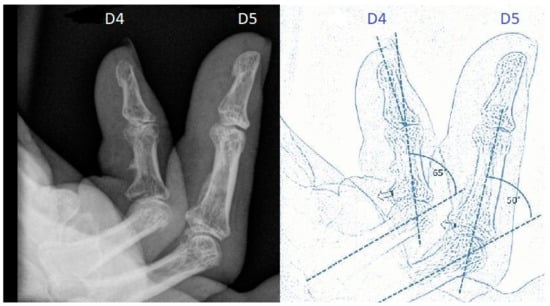

Between January 2003 and May 2020, a total of 724 fingers with DD were surgically treated in our Department of Plastic and Hand Surgery (Figure 4). During this period, 55 fingers of 53 patients with severe DD Iselin grade III–IV (Figure 5 and Figure 6) were operated upon.

Figure 6. Preoperative X-ray of stage IV flexion deformity and schematic drawing.